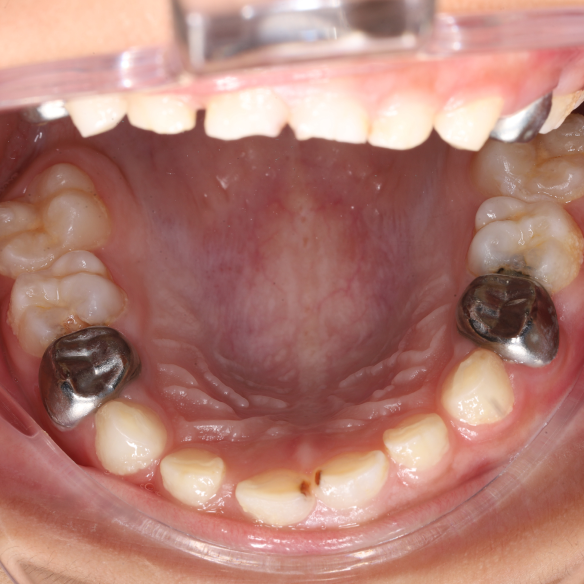

SSC (Stainless Steel Crown) là mão răng bằng thép không gỉ, được thiết kế sẵn với nhiều kích cỡ khác nhau, thường dùng để phục hồi răng sữa đã bị sâu lớn hoặc tổn thương nặng. Đây là một dạng phục hình toàn phần bao phủ toàn bộ thân răng, giúp bảo tồn và duy trì chức năng của răng sữa cho đến khi thay răng vĩnh viễn.

Mão SSC giúp bao phủ toàn bộ thân răng, giảm nguy cơ nứt vỡ và tái nhiễm khuẩn.